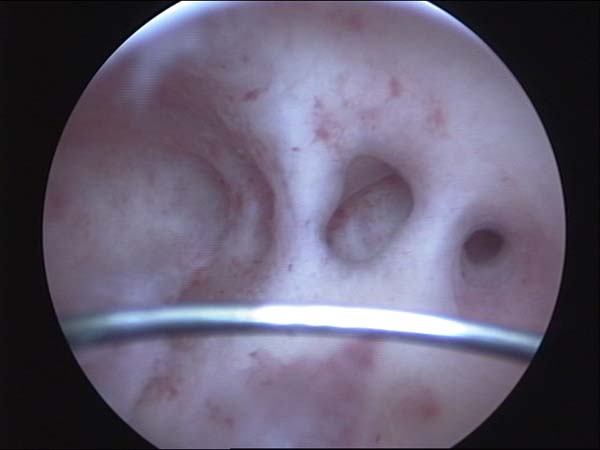

- Hystéroscopie - Hystéroscopie pour l'infertilité

- Clips vidéo de l’hystéroscopie

- Photos de l’hystéroscopie